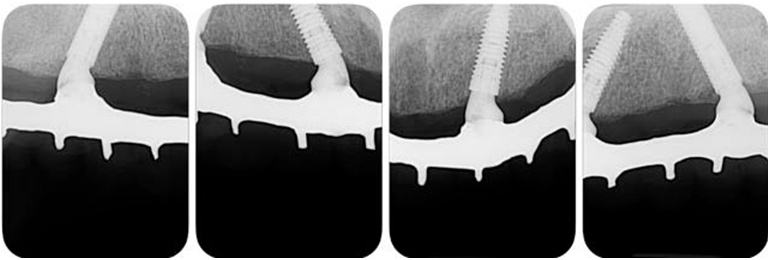

The patient returned with 14 days post-surgery to remove the suture and assess the clinical and radiographic condition of the rehabilitation. After 30 days and 6 months, success of implants and rehabilitation, favorable remodeling of the peri-implant tissues and satisfactory aesthetic and functional conditions were observed (Figure 6 and Figure 7).

Longer implants results in a reduction in stress transmitted to the bone, both in immediate and late loading protocols (16). With the evolution of implantology, extra-long implants of 20 to 25 mm were developed (8), which increased the probability of immediate loading of the prosthesis, satisfying the patient both functionally and aesthetically (7,8). In the present case report, the implants had a diameter of 3.75mm, and presented two different lengths, two were 13-mm-long implants (anterior region) and two were extra-long 20-mm implants (posterior regions). As a result, the apical anchoring of the implants occurred in the paranasal bone. The increased length of the implants can be important, since it has been reported that in a combination of low bone quality of the upper jaw and exposure to high occlusal loads, rehabilitation with short implants represents one of the most frequent causes of failure (17). Therefore, the placement of posterior long-length implants was an important factor for the cortical anchoring and the installation of the immediate prosthesis.

Extra-long implants placed tilted have been recommended to obtain high levels of primary stability in the upper jaw arch, avoiding bone graft procedures (18). From a biomechanical point of view, this situation can be extremely important (18). The tilted placement of the implants and the angled abutments provided the decrease in the length of the cantilevers in this case report, an important factor to avoid fractures of the metal bar (19). In addition, radiographic images have shown that the remodeling of the upper jaw bone around tilted implants is minimal (20).

The number of implants and positioning has also been the subject of studies on complete implant-supported rehabilitation (20,21). The compressive forces applied to the anterior and distal implants are the same in configurations with 4, 5 or 6 implants, provided that the distal implants are close to the molar region (18,20). In another study it was reported that the use of 4 implants towards the midline, including 2 implants placed V-shaped on the nasal crest and 2 implants placed on a M-shaped point on the piriform edge bilaterally, showed good stability after 1 year (20). In the current case report, the distal implants were placed tilted, being positioned closer to the molar region, reducing the cantilever, with the intention of providing a more favorable stress distribution on the prosthesis, implants and bone (7,16).